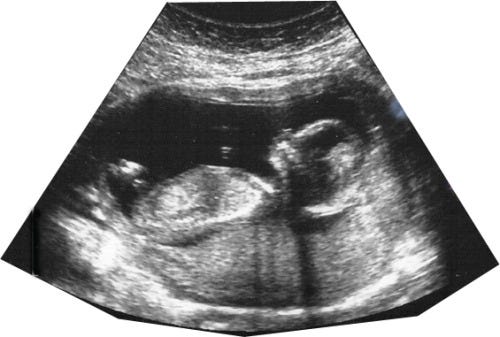

Un nuevo fenómeno ha capturado a Estados Unidos - las parejas jóvenes que están esperando niños están publicando fotos de sus bebés antes de nacer en línea o compartiéndolas con otras personas en sus iglesias e incluso en público. Cada imagen representa al bebé todavía en el vientre de la madre.

Quizás soy un tipo aburrido y constipado, chapado a la antigua, pero ¿no es eso sagrado? A medida que nuestra casa comenzó a ser bendecida con hijos, nunca se me cruzó por la mente mostrar esa imagen a los demás. Cada bebé es un regalo de Dios, escondido en el carácter sagrado del vientre de la madre hasta el día de su nacimiento.